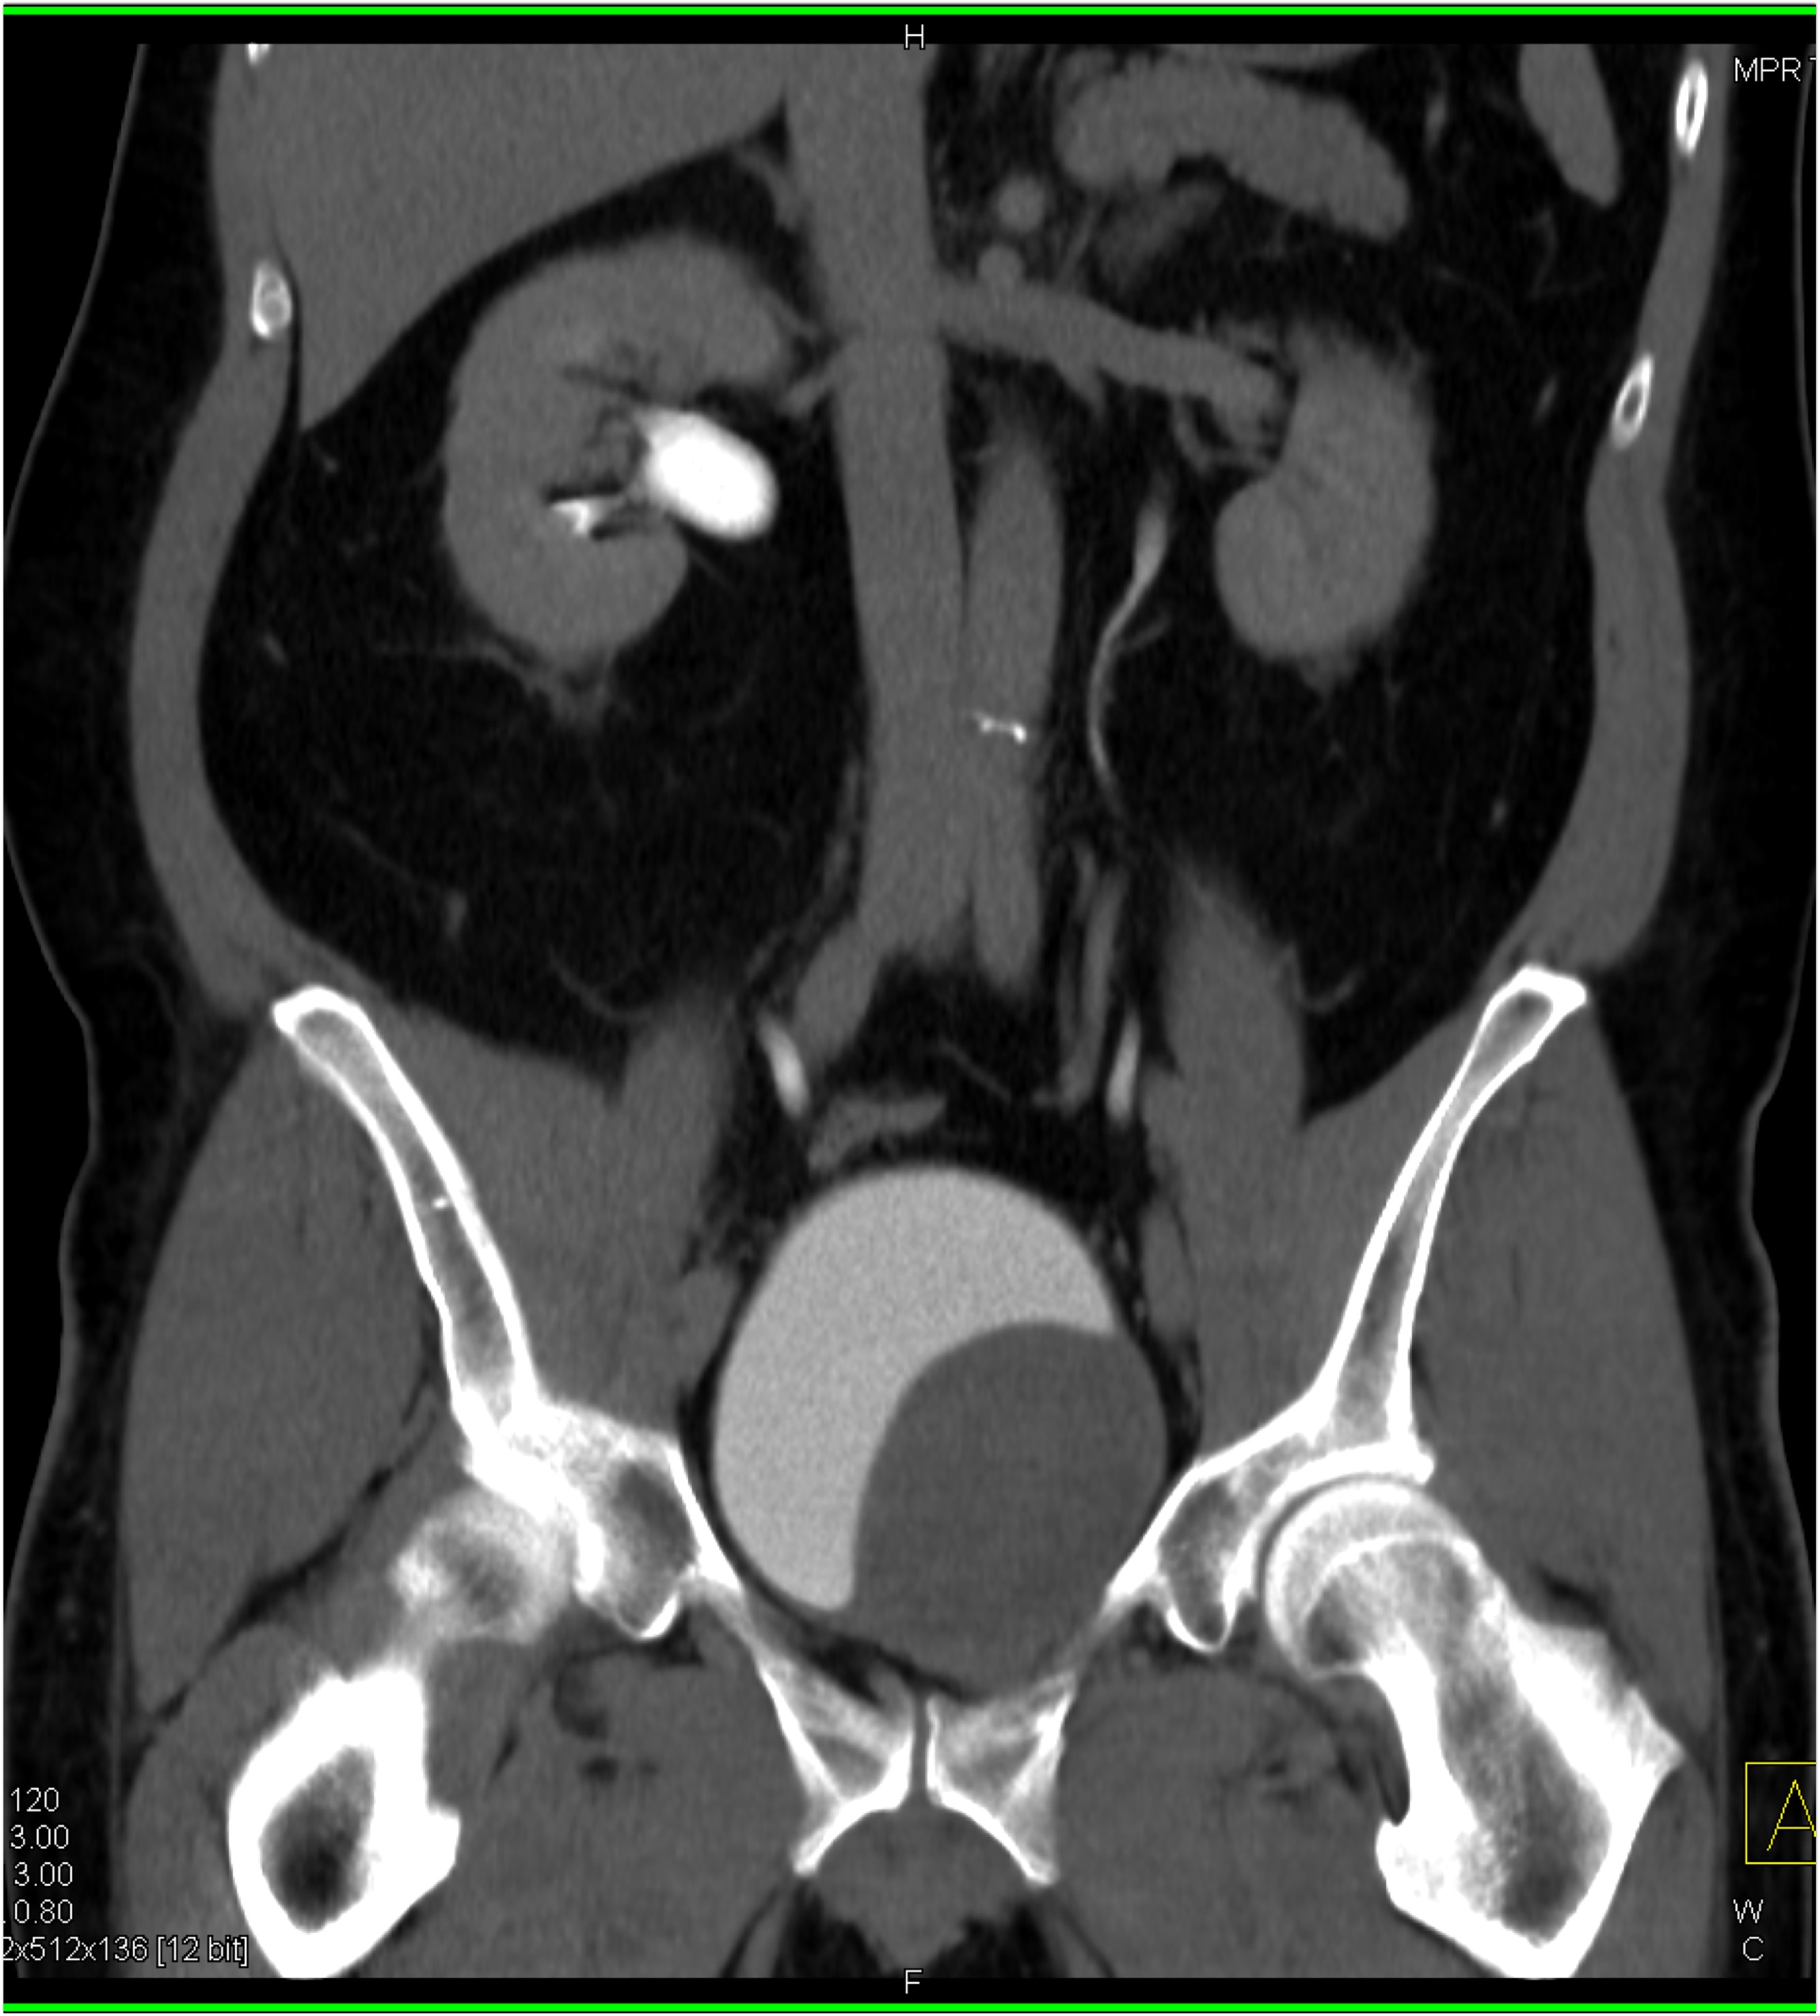

7) In this patient with pelvic pain the best diagnosis is?

lymphoma

silicon injection into buttocks

neurofibromatosis

intramuscular hemorrhage